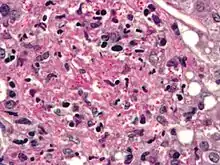

Aspergillosis. H&E stain.

The most common pathogenic species are Aspergillus fumigatus and Aspergillus flavus. Aspergillus flavus produces aflatoxin which is both a toxin and a carcinogen and which can potentially contaminate foods such as nuts. Aspergillus fumigatus and Aspergillus clavatus can cause allergic disease. Some Aspergillus species cause disease on grain crops, especially maize, and synthesize mycotoxins including aflatoxin. Aspergillosis is the group of diseases caused by Aspergillus. The symptoms include fever, cough, chest pain or breathlessness. Usually, only patients with weakened immune systems or with other lung conditions are susceptible.[1]

The spores of Aspergillus fumigatus are ubiquitous in the atmosphere. A. fumigatus is an opportunistic pathogen. It can cause potentially lethal invasive infection in immunocompromised individuals.[10] A. fumigatus has a fully functional sexual cycle that produces cleistothecia and ascospores.